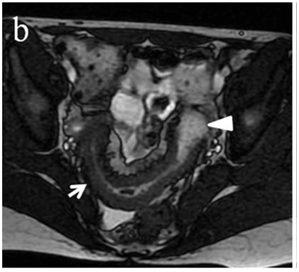

Figure 4 (a) Coronal SSFSE (singleshot fast spin echo) T2-weighted image with fat suppression (b) axial FIESTA (fast imaging employing steady-state acquisition) image show wall thickening (white arrow) and stenosis of the lumen in the terminal ileum. Note the prestenotic dilatation in b (white arrowhead). (c) Neoterminal ileum wall is thickened and has high signal on diffusion-weighted (DW) image (b= 800 s/mm2) (white arrow) and dark signal (black arrow) on the apparent diffusion coefficient (ADC) map in (d) indicating restricted diffusion. (e,f) ADC value measurement from the wall of the terminal ileum on magnified DW image. (e) and corresponding ADC map (f): ADC value = 1.20 × 10-3 mm2/s

Figure 5 Comparison of coronal (a) and axial (c) DWI sequences with the respective

after contrast medium injection (b, d).